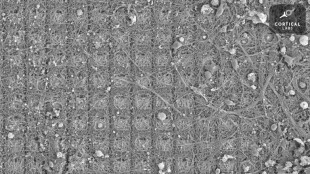

Des neurones cultivés dans une boîte de Petri sont capables d'apprendre à jouer à Pong, le grand classique des jeux vidéo, faisant ainsi preuve d'un "comportement intelligent et doué de sensations", selon des chercheurs en neurosciences australiens.